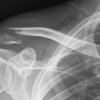

Oreffo's team has tested the polymer using mice that had parts of their femur bones removed. The hole was of a size "that won't heal normally," he said. "We can put these scaffolds into that [gap] and look at their repair over four to eight weeks."

When the scaffold was seeded with human bone stem cells, the bone healed faster, but even without the stem cells, the mice's bones began to fill in along the scaffolding structure.

In humans, the structure should serve to repair bone breaks that are too severe to heal on their own. "If you've had a car accident where you've had significant bone breaks ... ideally, you want your own stem cells in there," Oreffo said. "This is a real opportunity: A scaffold that can be colonized with the patient's own stem cells."